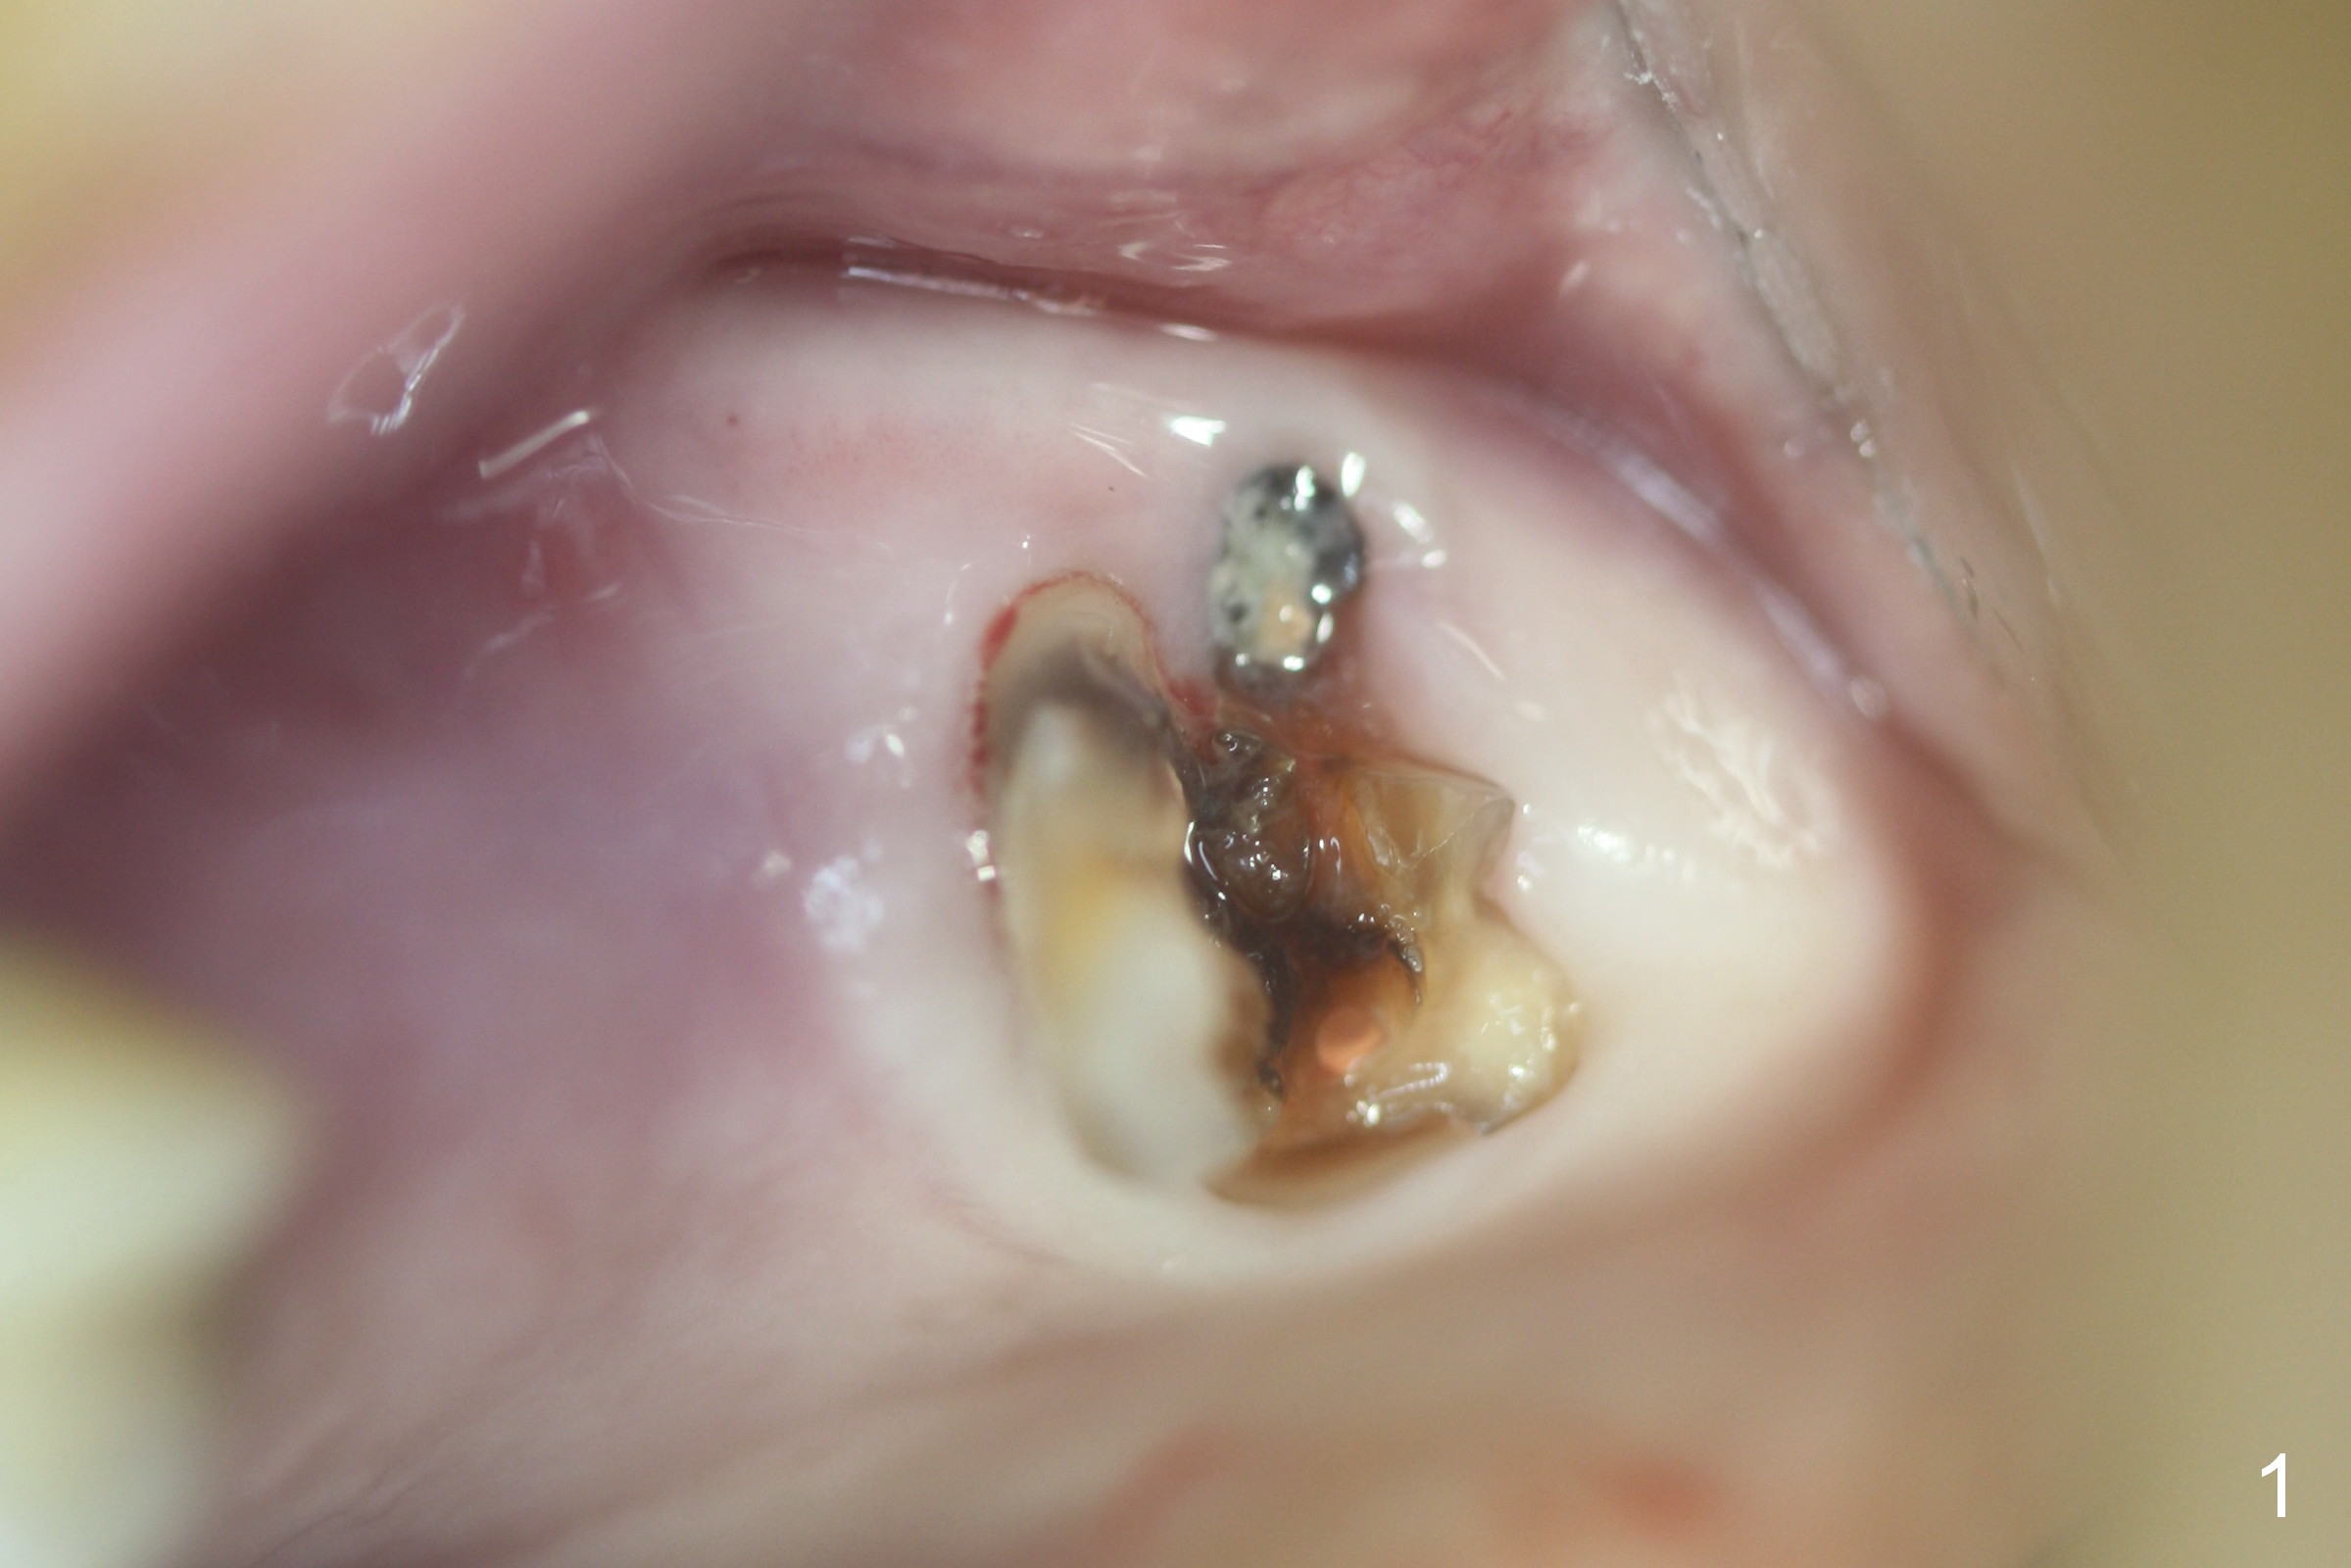

Fig.1,2 show the close relationship of the upper flipper and the residual roots at #15.  Atraumatic extraction using periotomes and surgical sectioning still results in perforation of the mesiobuccal socket (Fig.3 >).  The distobuccal one is shallow, while the septum is small.  It appears that the palatal (Fig.3 P) socket is the most ideal recipient site for the immediate implant and is expanded with Magic Osteotomes until 4.3 mm (Fig.4,5) with the coronal end pushed as buccal as possible.  After placing allograft for sinus lift (Fig.6 >), a 5x11 mm IBS implant is placed with insertion torque ~ 50 Ncm.  A 6x4(3) mm pair abutment is placed, followed by bone graft in the remaining sockets (Fig.6 *) and by Osteogen plug (Fig.7 *).  Finally the socket is sealed by applying acrylic over the abutment (Fig.8).  While the acrylic is setting, the flipper is seated and excess acrylic is removed and pushed away from the flipper (Fig.9).  Advise the patient not to wear the flipper.  If it is being worn, there will be minimal contact between the flipper and the immediate provisional.